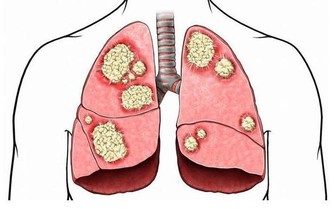

2.睡前吃油炸食物

因為油炸食品對肝臟的損害是非常大的。油脂和飽和脂肪酸的堆積導致了脂肪肝。常吃油炸食品不僅不利腰圍、讓膽固醇水平升高,而且有損肝臟。吃油炸食品一個月,對肝臟的傷害即類似肝炎。